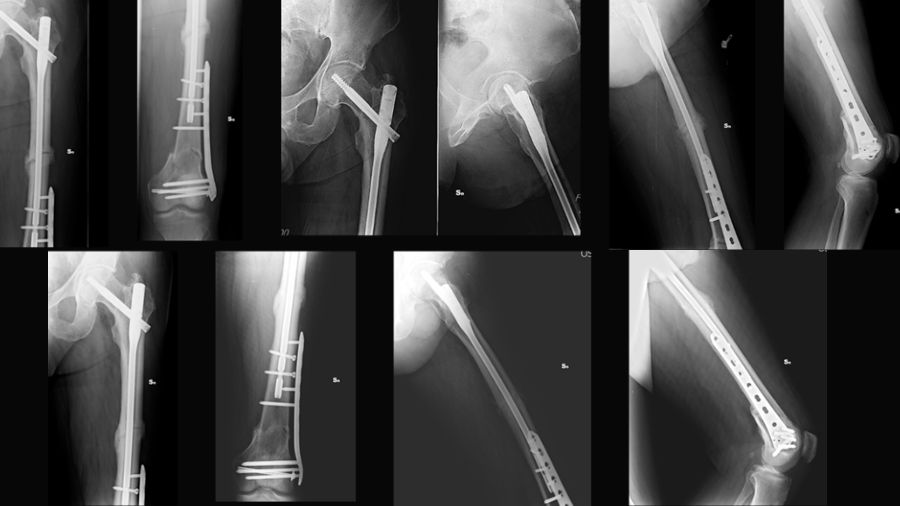

This case report describes a high-energy trifocal femoral fracture (intracapsular femoral neck, femoral shaft, and complete distal articular femur) treated with an intramedullary nail, free cannulated screws, and a LISS plate.

This combination of implants, not previously reported in the literature, allowed for an anatomical reduction with absolute stability of the distal periarticular fracture and a functional reduction with relative stability in the other two fractures (shaft and femoral neck).

After resolving the pulmonary complications, the definitive surgery was performed in a single stage, step by step:

- Kirschner wires were used to stabilize the femoral head, preventing further displacement

- Cannulated screws were applied to fix the intra-articular distal femoral fracture

- A nail with static distal locking was inserted

- A LISS plate was applied

We used an antegrade reconstruction nail for the femoral neck and diaphyseal fractures, cannulated screws for the distal intra-articular fracture, and a LISS plate for the supracondylar femur fracture. This combination prioritizes articular fractures with direct reductions and optimally treats the femoral shaft with intramedullary nailing.